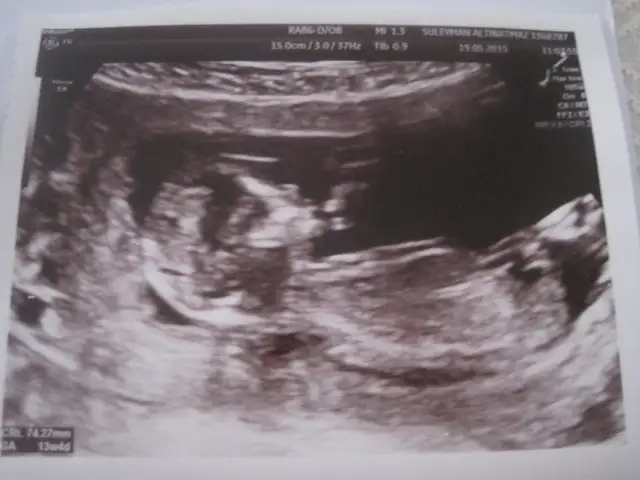

Eki Görüntüle 1532537 Canim buda normal ultrasyon resmi simdi belli oluyomu

Canım kordonunun hemen altında bir çıkıntı daha var. Yukarı açılı duruyor. Bu erkek bebek nubudur. Eğer görüntüden kaynaklanan bir sıkıntı yoksa bence bu bebek erkek. Çünkü nubu o kadar Yukarıdan başlayıp, yukarı açılı olan ancak erkek bebek olabilir :) ayrıca neye göre kesin kız dedi ki?